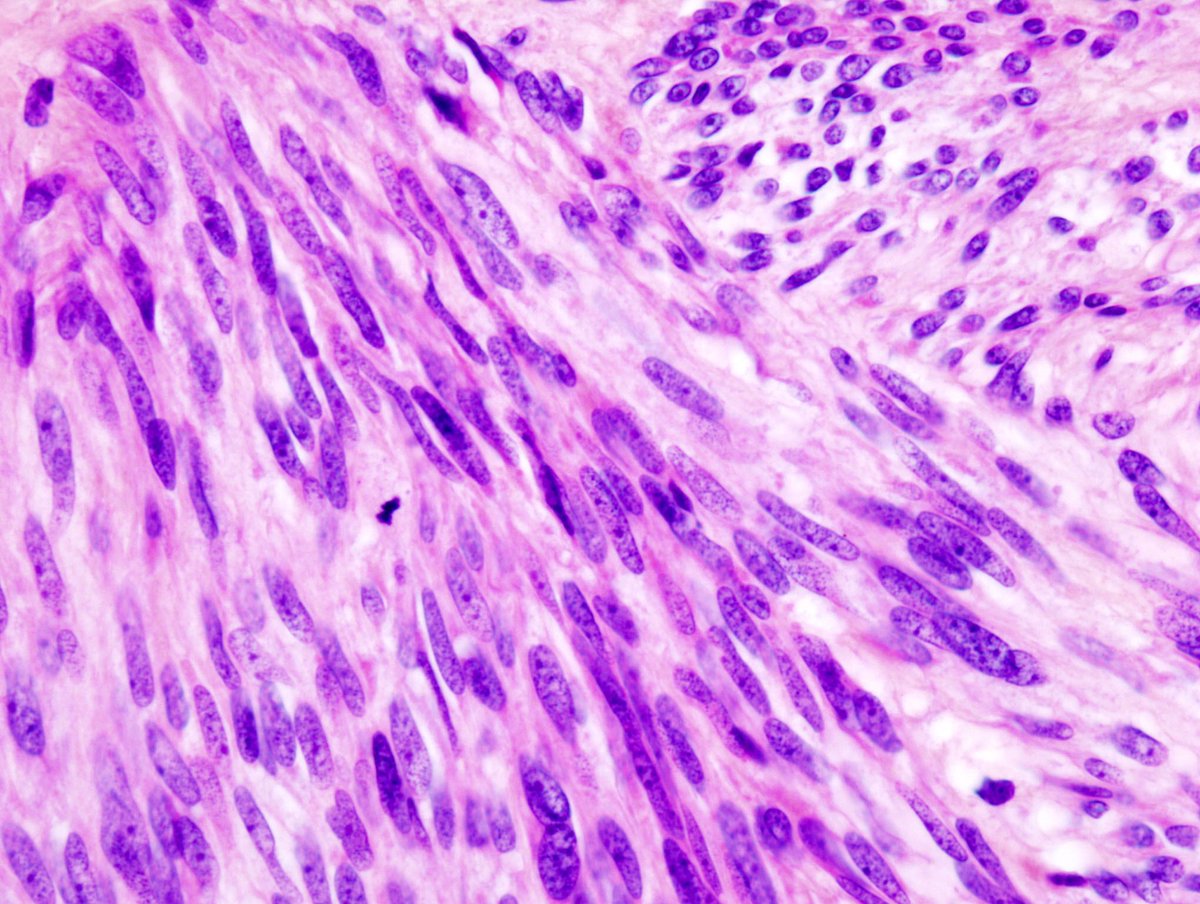

خلاياها تشبه الى حد كبير الخلايا العضلية و لكن في شكل مغزلي (spindle). و يتم تحديدها ببعض الصبغات المناعية مثل ckit/CD117 كما هو موضح في الصور